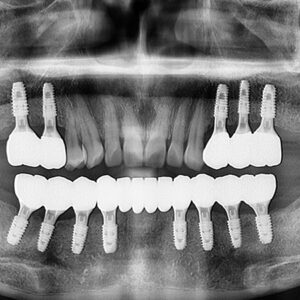

울산안아픈치과 신경치료 후 염증 치아재식술로 해결해요! 안녕하세요. 울산안아픈치과 뉴욕연합치과입니다. 임플란트가 워낙 보편화되고 선호하는 분들이 많아지고 있지만, 자연치아를 살리고자 하는 수요도 급상승하고 있는 추세입니다. 위 환자분은 충치가 많이 진행되어 신경치료한 치아를 사용하고 있었습니다. 하지만, 오랜 기간이 지나 치아 뿌리 끝에 염증이 생겨 발치를 권유받았는데요, 발치를 하더라도 치아 뿌리만 손상 더보기…